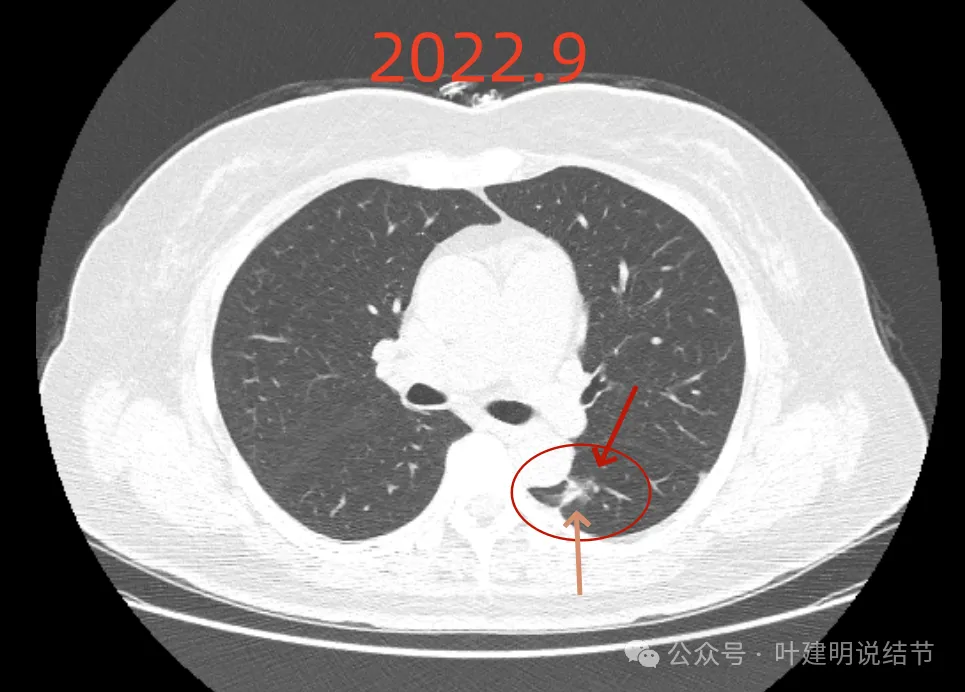

最后看2024年复查的影像:

病灶出现,密度不纯,毛刺细长。

轮廓稍显模糊,密度不均,毛刺偏长。

病灶膨胀感较之前明显;与主动脉壁之间缝隙不太明显了。

实性成分似乎较前增多,胸膜略有牵拉。

膨胀性较前明显,基本实性。

与主动脉壁贴得紧了,但褐色所指处边缘还是较为平直。

与主动脉壁之间紧贴了,对侧出现了细毛刺,整体基本都是实性密度了。

实性成分占比增加,邻近结构受压,边缘毛刺出现。

表面不平,密度高,与主动脉间隙消失。

现在较2年前有进展,显示了更多的恶性影像特征,整体密度也增加,膨胀性也明显起来,并对邻近结构有压迫,表面不平毛糙。持续存在的实性为主的结节随访进展,并显示出更多恶性特征,那就得高度怀疑恶性,而且不宜再随访了。